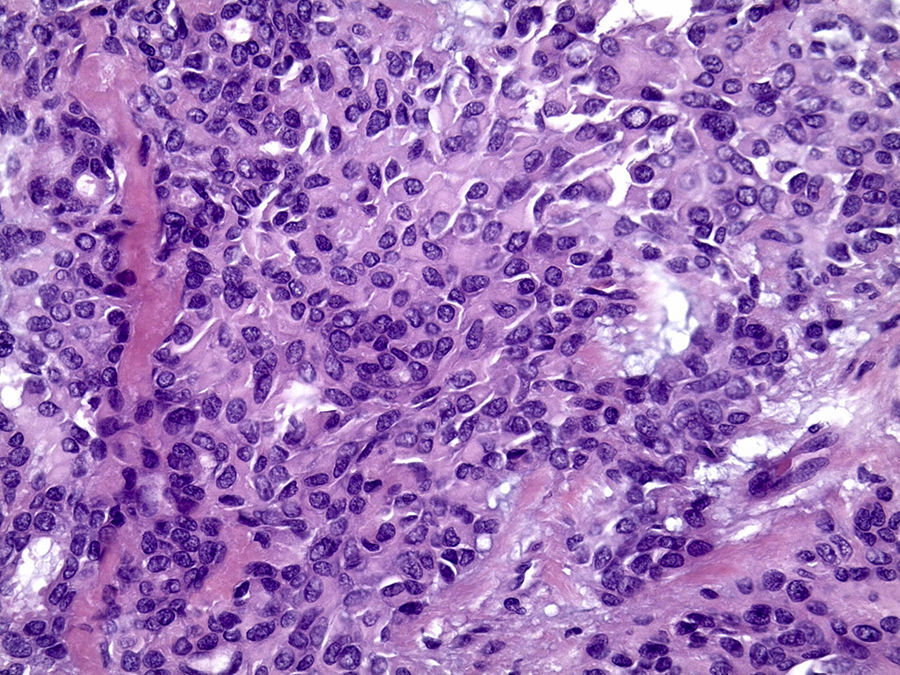

Os cortes histológicos, corados em hematoxilina e eosina, mostraram neoplasia de glândula salivar benigna, constituída por células epiteliais e mioepiteliais, parcialmente envolvida por fina cápsula de tecido conjuntivo fibroso (fig. 5). As células epiteliais encontravam‐se formando lençóis ou estruturas ductiformes, enquanto as células mioepiteliais formavam áreas mixoides, hialinas (fig. 6) ou exibiam aspecto plasmocitoide (fig. 7). O diagnóstico de adenoma pleomórfico foi confirmado. Paciente queixou‐se de desconforto no palato quando se alimentava, durante as 2 primeiras semanas após cirurgia. O paciente está sendo acompanhado clinicamente e, 2 anos após a cirurgia, não apresenta sinais de recidiva da lesão (fig. 8).

Os cortes histológicos mostraram neoplasia benigna de glândula salivar, envolvida por cápsula de tecido conjuntivo fibroso (fig. 14). O parênquima neoplásico é constituído por células epiteliais dispostas em lençóis e estruturas ductiformes, além de células mioepiteliais formando áreas mixoides e hialinas (fig. 15) ou apresentando‐se com morfologia plasmocitoide (fig. 16). O diagnóstico de adenoma pleomórfico foi confirmado. A paciente relatou ausência de dor no pós‐operatório e manteve utilização da placa de acrílico por 4 semanas. A paciente encontra‐se em acompanhamento e o exame clínico após 2 anos da remoção cirúrgica mostrou adequada cicatrização e ausência de sinais de recidiva da lesão (fig. 17).